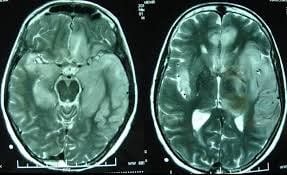

Chụp phim não xuất hiện màu đen bất thường

Chào bác sĩ! Hôm trước em có chụp phim và phát hiện có cục màu đen bên phía não trái. Vậy đây là dấu hiệu của bệnh gì ạ? Mong bác sĩ tư vấn giúp em, xin cảm ơn!